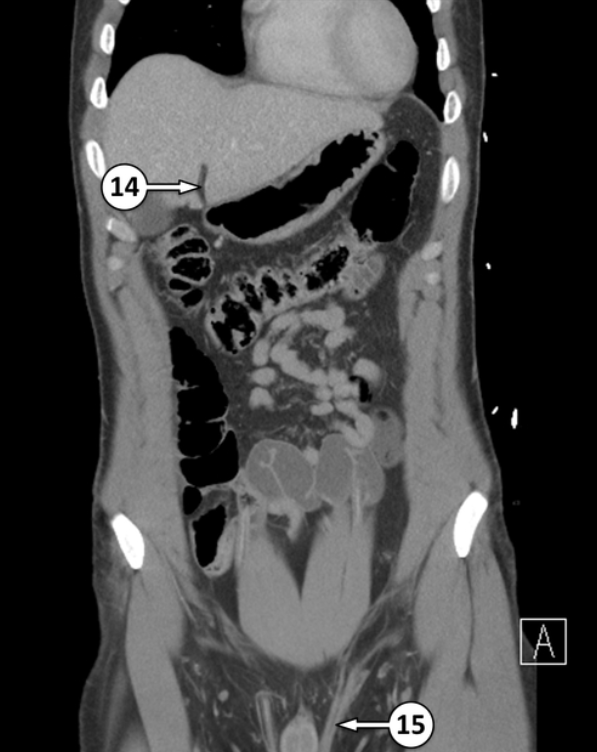

Please label 14 and what is it’s function

Falciform ligament, and it’s separates the liver into it’s anatomical left and right lobes on the anterior view

No. 16 is ileum of the small intestine. Please label the epithelium type and it’s function

Simple columnar + peyer’s patches

absorbs remaining nutrients